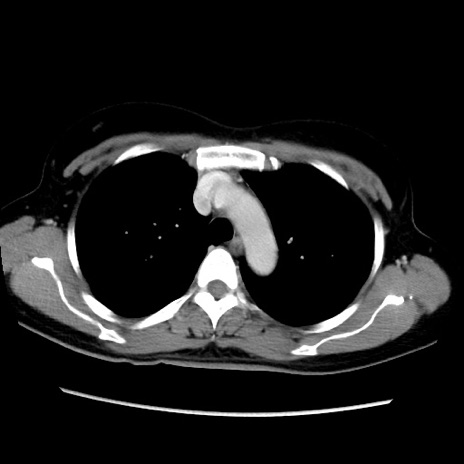

症例39(横断像)

【症例】40歳代女性

【主訴】上下腹部痛

【現病歴】2日目から下腹部痛あり。夜間は痛みで眠れなかった。昨日より上腹部痛と下痢が出現。臥位で痛みは軽快したため、休んでいた。本日になって臥位でも立位でも痛みが強くなってきたため救急要請。

【既往歴】子宮内膜症

【身体所見】部:平坦・軟、左上下腹部に圧痛あり、反跳痛あり。

【データ】WBC 21800、CRP 26.78